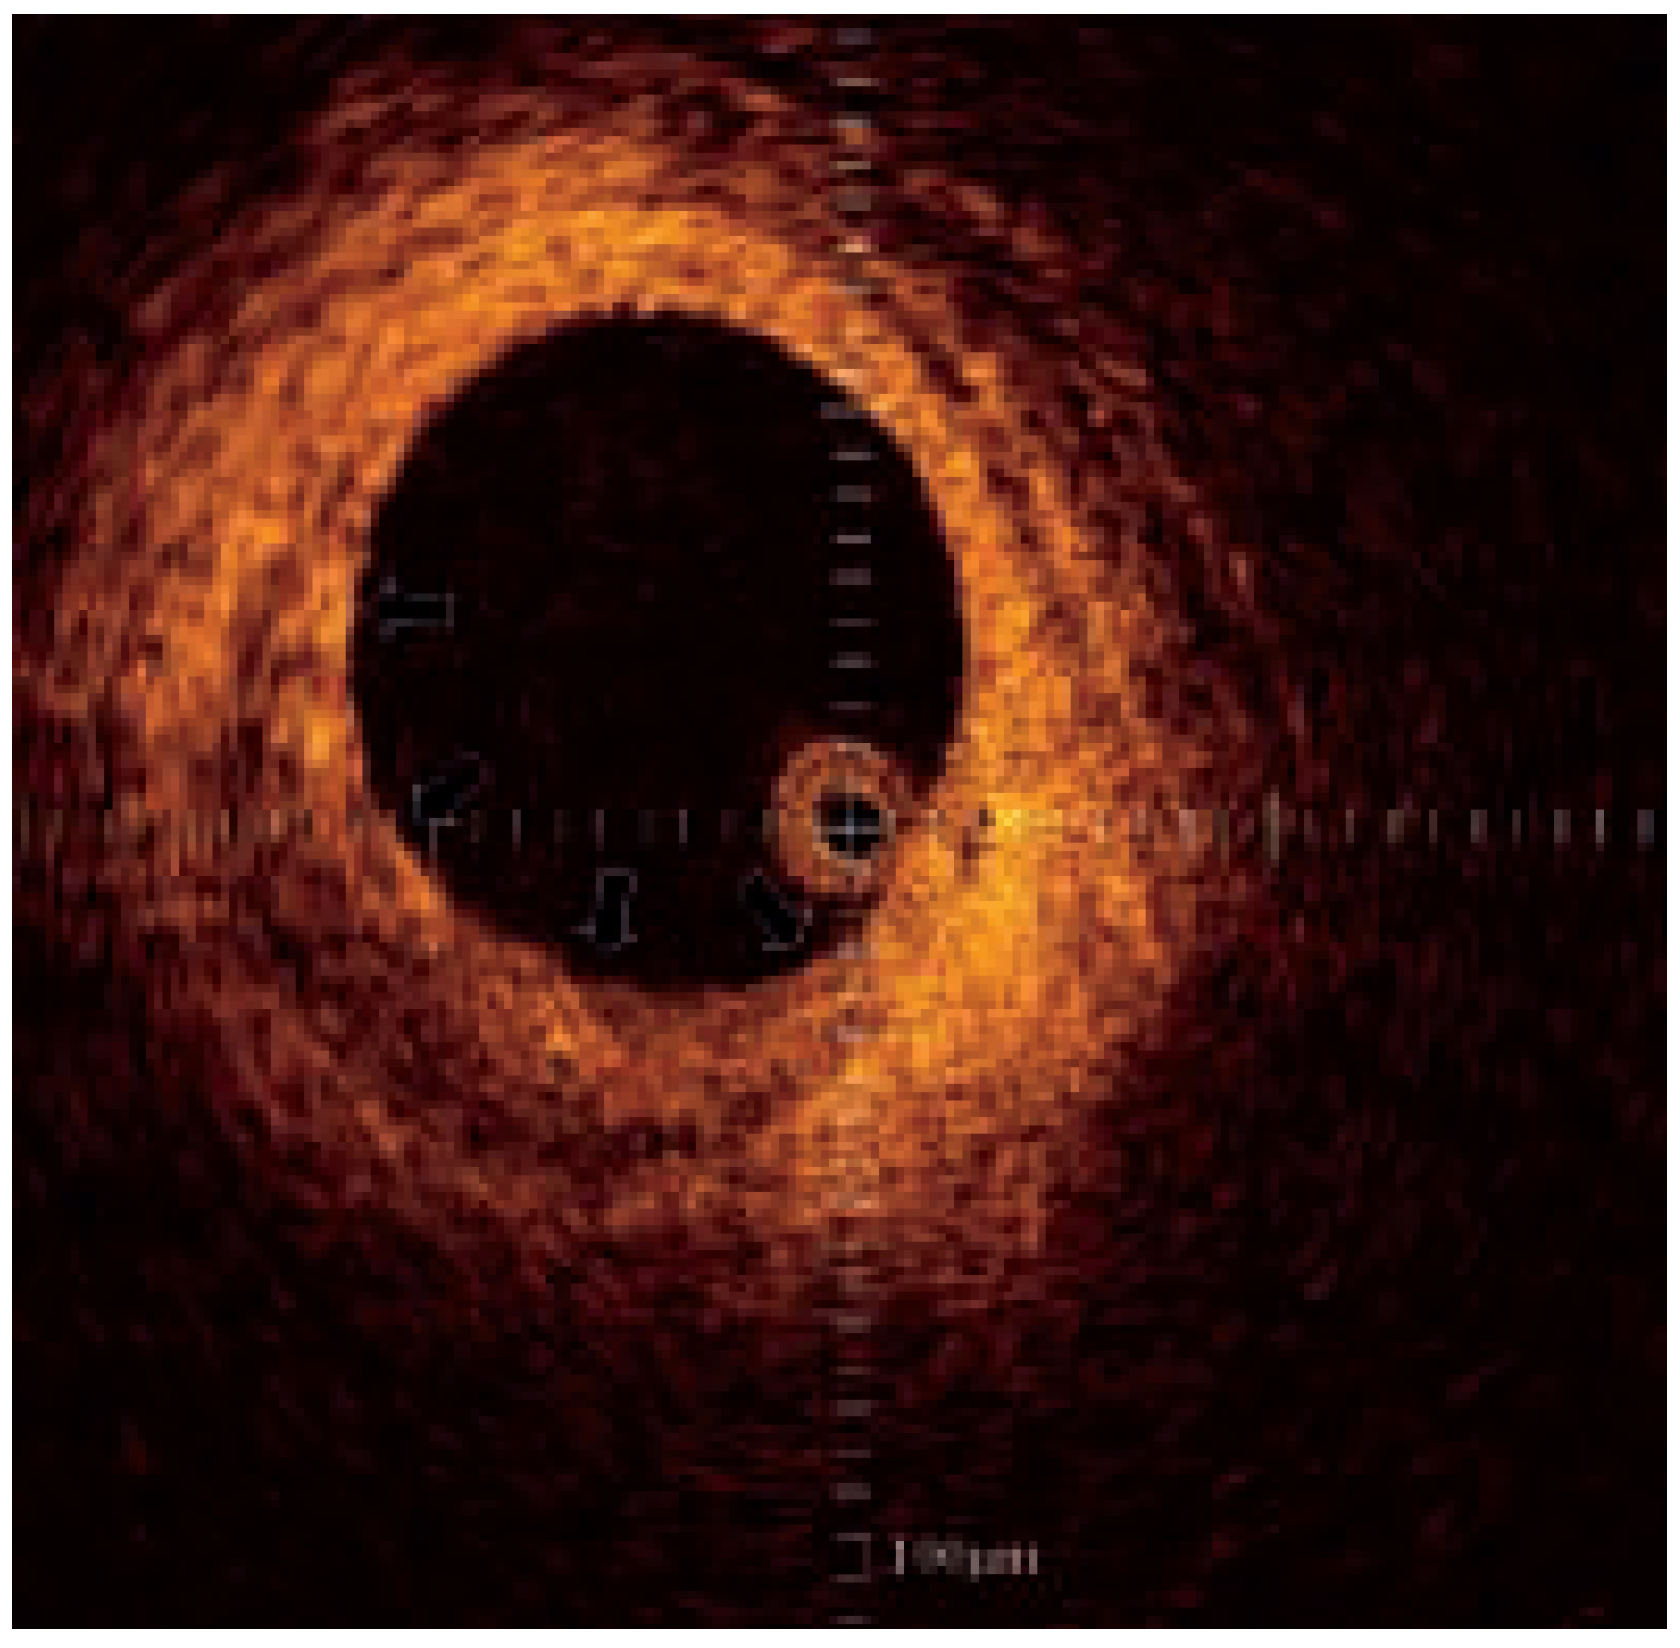

Optical coherence tomography

- Yabushita, H.; Bouma, B.E.; Houser, S.L.; Aretz, T.; Jang, I.K.; Schlendorf, K.H.; et al. Characterization of human atherosclerosis by optical coherence tomography. Circulation 2002, 106, 1640–1645. [Google Scholar] [CrossRef]

- Jang, I.K.; Bouma, B.E.; Kang, D.H.; Park, S.J.; Park, S.W.; Seung, K.B.; et al. Visualization of coronary atherosclerotic plaques in patients using optical coherence tomography: comparison with intravascular ultrasound. J Am Coll Cardiol 2002, 39, 604–609. [Google Scholar] [CrossRef] [PubMed]